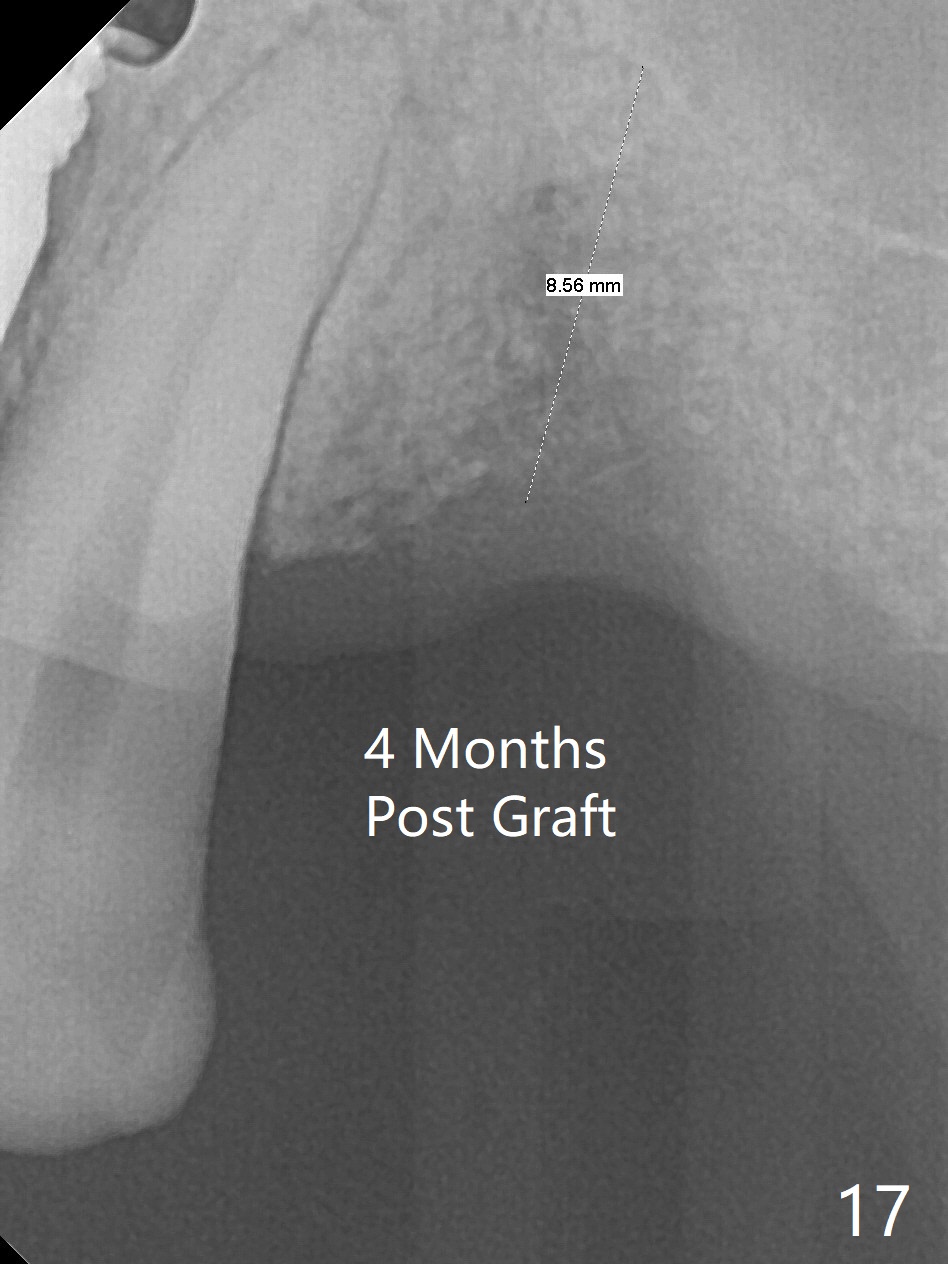

The bone density of the site is low 4 months post bone graft (Fig.17,18). Use the existing guide, but incision will be made. The osteotomy will be underprep. Take 5x5 cm CT for bone width and height after use of 2.2x7.3 drill with 1 or 2 O-rings. Prepare sinus lift, including water pump and bone graft, especially distal. Place healing screw and suture. Prepare PRFx2.